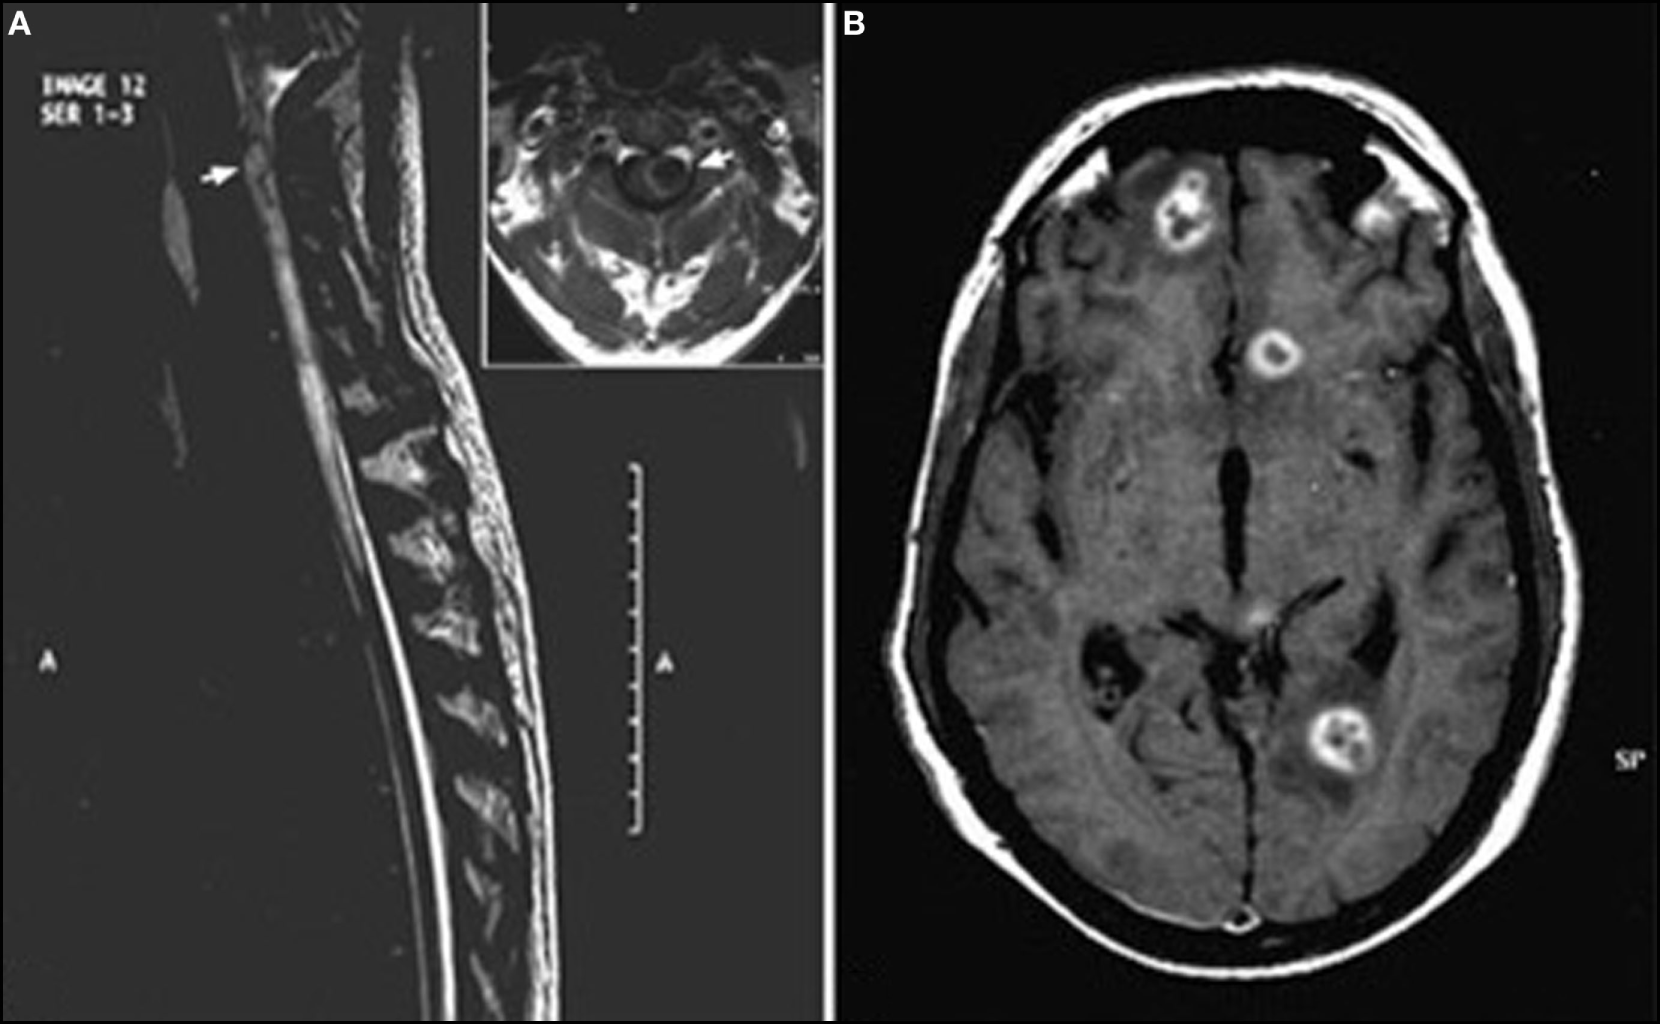

Figure 2

Encephalomyelitis (50) (A) T2-weighted sagittal image of spine showing a hyperintense lesion (arrow) with extensive perilesional edema in the upper cervical cord. Inset highlights large lesion (arrow) with peripheral hyperintense rim and perilesional edema causing expansion of cervical cord. (B) T1-weighted axial post-contrast image of brain shows multiple ring-enhancing lesions in bilateral frontoparietal deep white matter with nodular enhancement of the wall seen in left frontal lesion. This image has permissions for use.

Magnetic resonance imaging findings are not specific, showing single or multiple subcortical, cortical, or white matter hyperintense lesions on FLAIR and T2WI, usually isointense or hypointense in T1WI (Figure 1). Homogeneous or punctate enhancement after gadolinium injection was observed in nine cases, and single or multiple ring-enhancing lesions were described in four cases (Figure 2) (41, 42, 44, 50). Focal meningeal contrast enhancement, next to an active inflammatory lesion, was described in three patients (55, 59, 61). In the patient with obstructive hydrocephalus (61), brain MRI revealed hydrocephalus and leptomeningeal enhancement at the prepontine cistern, left cerebellopontine angle cistern, bilateral cerebral hemisphere, and a non-enhancing mass posterior to cerebral aqueduct. Imaging of the patients with vasculitis generally showed ischemic lesions; in four of the seven cases, diffusion-weighted imaging sequences were also performed demonstrating the presence of multifocal acute infarctions (62, 63, 66, 67). MRI angiography was performed only in one case (65) showing numerous segmental and irregular stenoses of the encephalic arteries; angiography (68) was also performed in one patient showing the occlusion of multiple small branches of the middle cerebral artery.